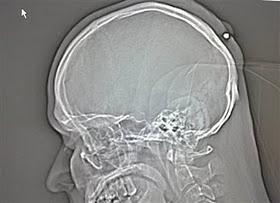

2. Orang yang ditembak di kepalanya tetapi baru tahu 5 tahun kemudian

Seorang pria yang hidup di Jerman hidup dengan normal dan baik-baik saja selama lima tahun tanpa menyadari ia telah ditembak di kepala. Peluru kaliber 0,22 ditemukan ketika orang itu pergi ke dokter untuk memiliki apa yang ia pikir merupakan kista .

Yang dia ingat adalah bahwa ia telah menerima pukulan ke kepala sekitar tengah malam di sebuah pesta Tahun Baru "di tahun 2004, atau 2005" tapi sudah lupa tentang hal itu karena ia "sangat mabuk."